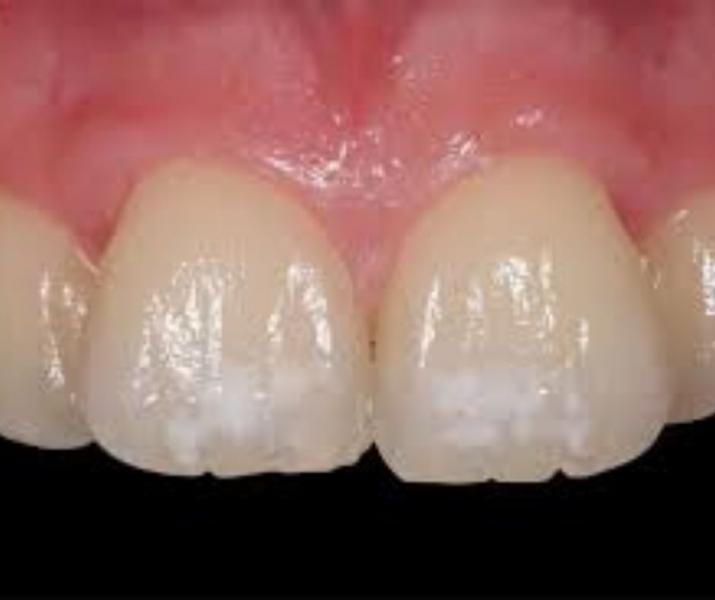

La hipoplasia dental es una enfermedad que afecta a los dientes y se manifiesta con un deterioro de la capa de esmalte. La primera consecuencia es que el diente queda desprotegido y con un color diferente con manchas blancas, amarillentas o marrones. También pueden aparecer pequeñas cavidades.

- Estéticamente para eliminar estos cambios de color se han de hacer coberturas de composite, o carillas de composite en sector anterior, o también carillas de cerámica para tapar estos cambios de coloración.